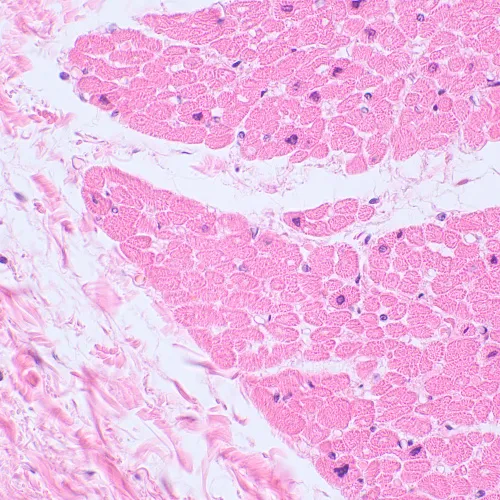

Mikroskop biologiczny MAGUS Bio 230TL to niezbędny przyrząd w laboratoriach kontroli sanitarnej, a także w ośrodkach diagnostycznych i badawczych. Mikroskop ma głowicę trójokularową oraz źródło światła przechodzącego (LED). Jest odpowiedni do obserwowania preparatów przezroczystych i półprzezroczystych. W konfiguracji podstawowej do obserwacji służy technika jasnego pola. Przy użyciu dodatkowych akcesoriów można stosować inne techniki obserwacji mikroskopowych, takie jak obserwacje metodą ciemnego pola, w świetle spolaryzowanym oraz kontrastu fazowego.

Kliniczne/laboratoryjne

Zastosowanie i wykorzystanie mikroskopu